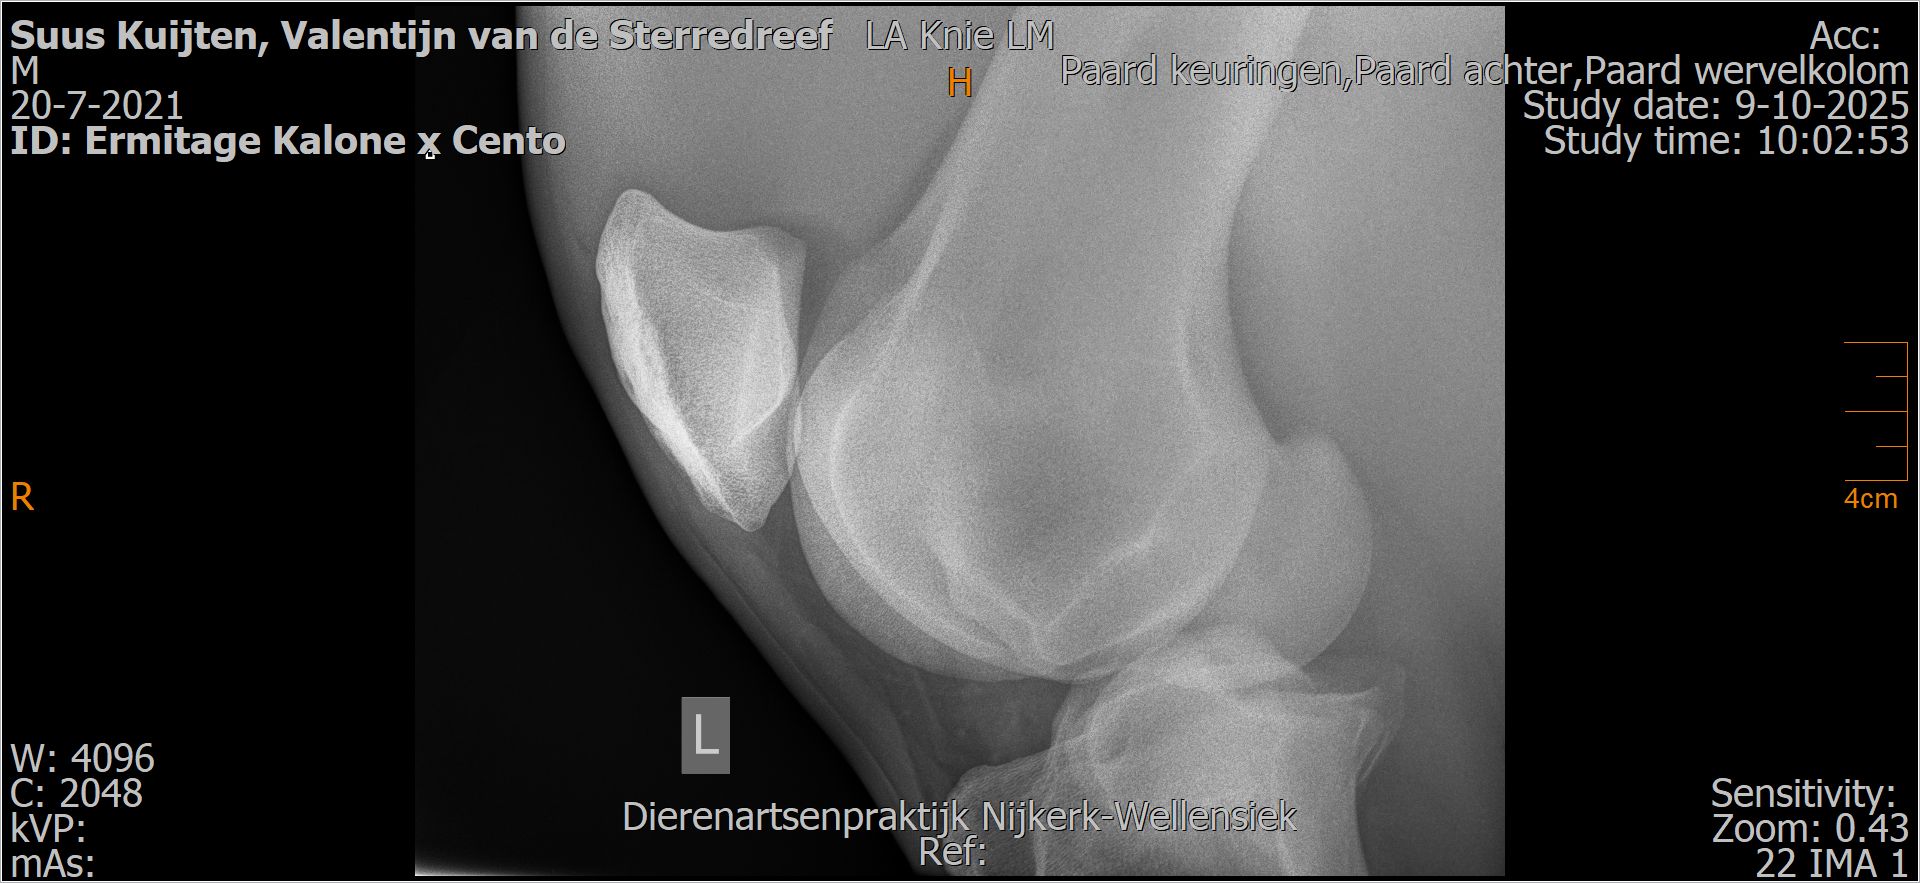

Valentijn van de Sterredreef

Leeftijd:

4

Röntgenfoto’s